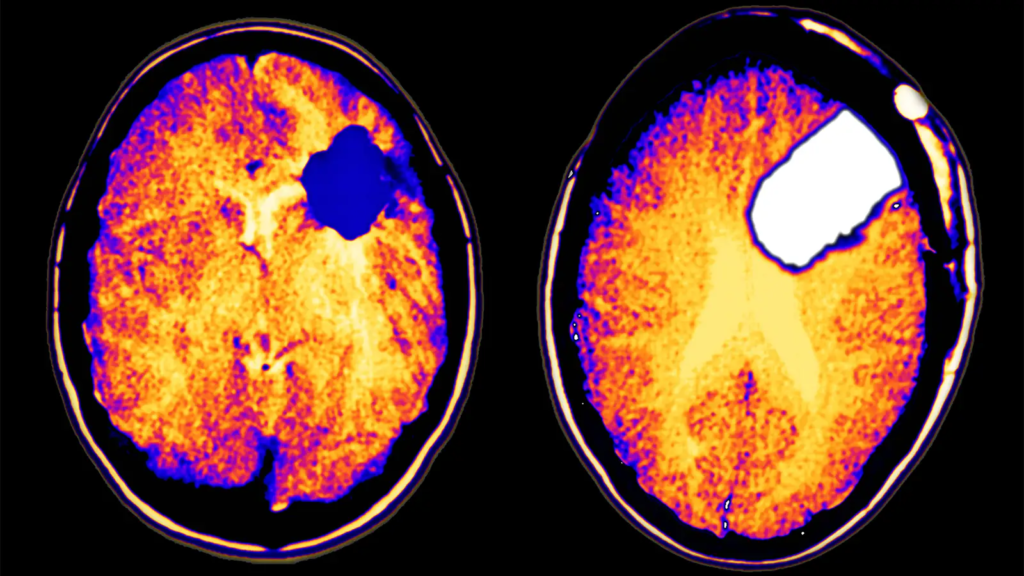

The anticipated expansion is primarily driven by the rising incidence of low-grade glioma cases globally and the growing demand for innovative and more effective treatment options. Low-grade gliomas, classified as Grade I or II tumors by the World Health Organization (WHO), are characterized by their slow growth. Despite their relatively indolent nature, these tumors often infiltrate surrounding brain tissues, posing significant challenges for complete surgical removal. This underlines the urgent need for advanced therapeutic solutions to improve patient outcomes.